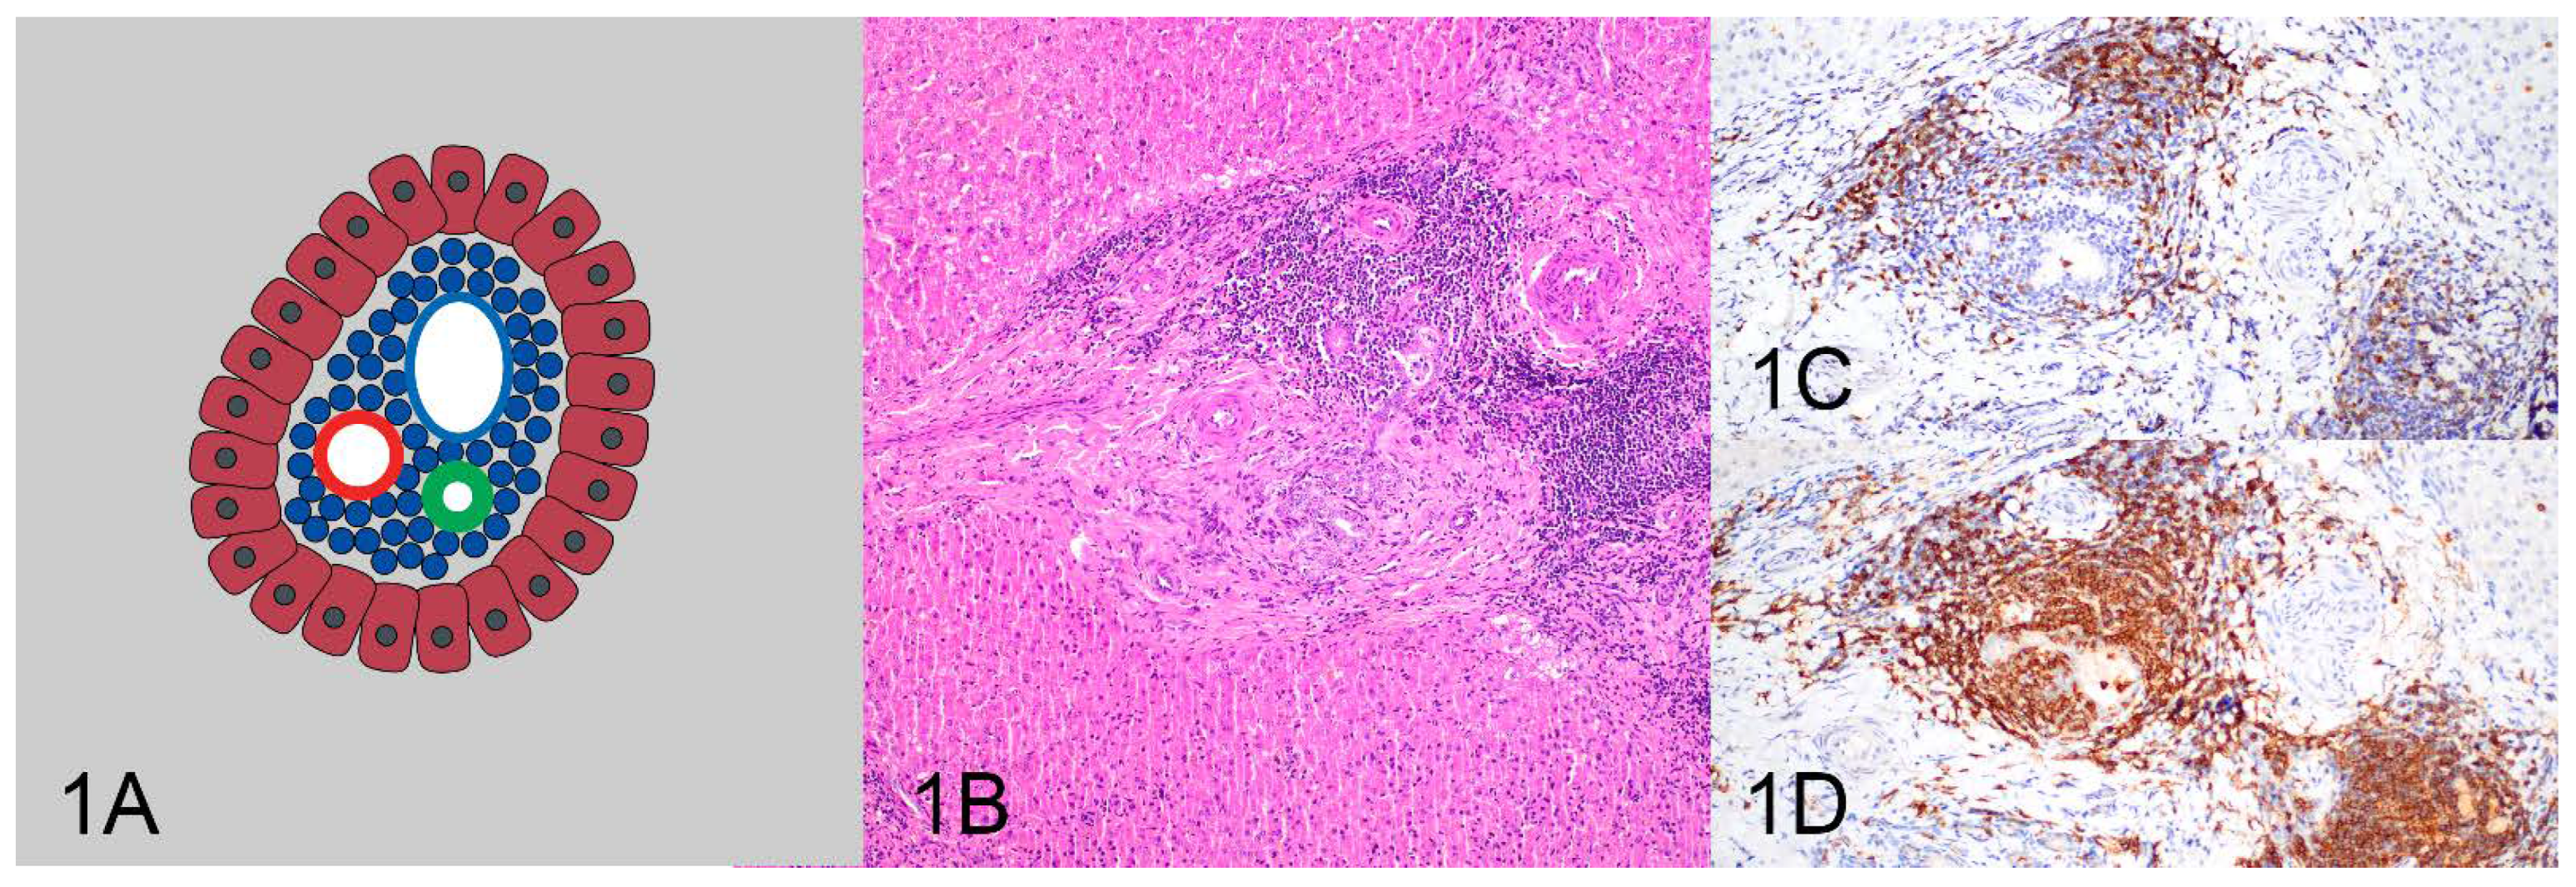

| Pattern 1: Tightly periportal | 15 (83.3%) | 3 (16.7%) | 18 (100%) |